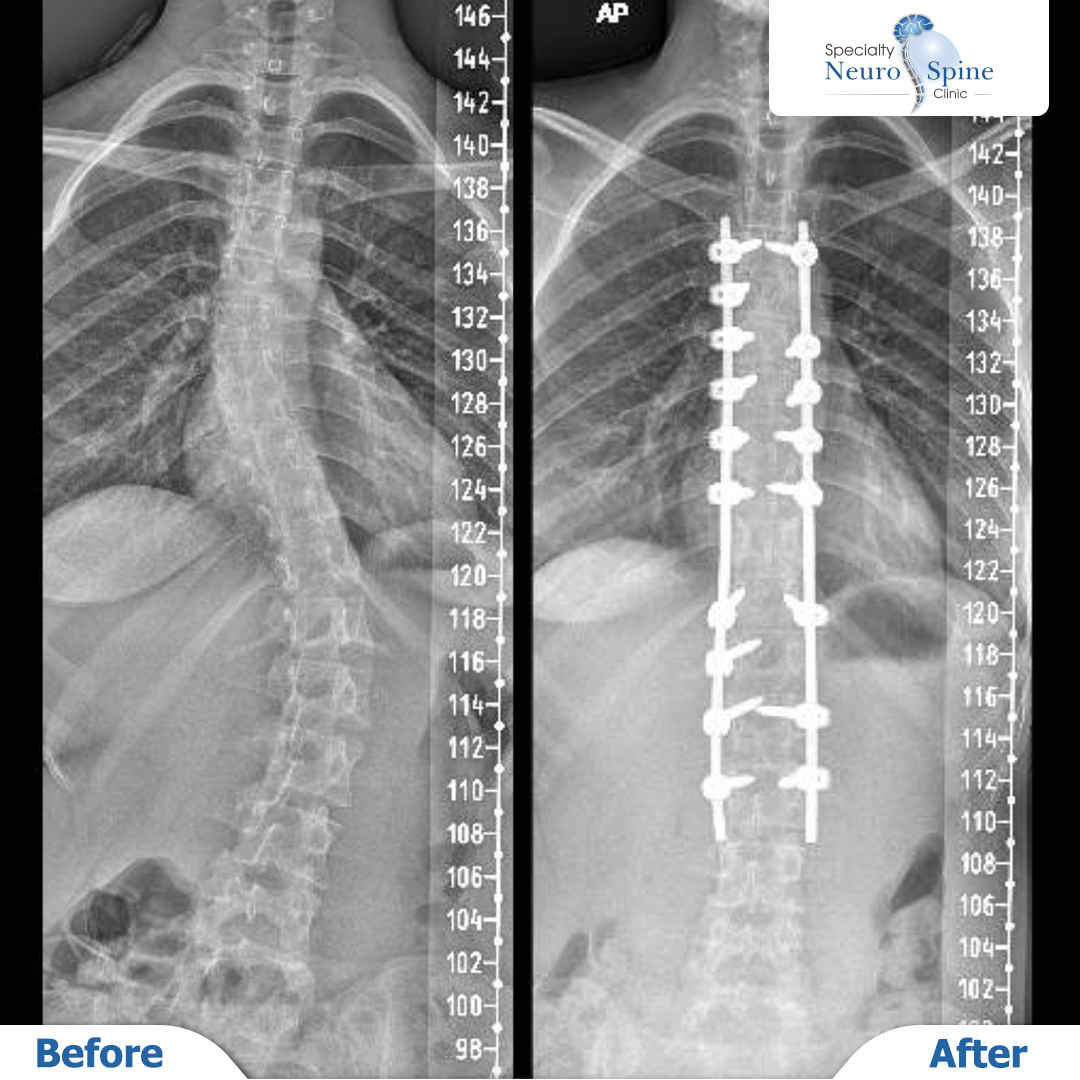

Now at 18, Luma has fully recovered and leads a normal, active life. She has returned to her favorite sports, including tennis and swimming, and recently won first place in a badminton championship.

Her inspiring journey is a testament to the power of early diagnosis, expert care, and advanced surgical techniques. We celebrate her success and wish her continued health and achievements!